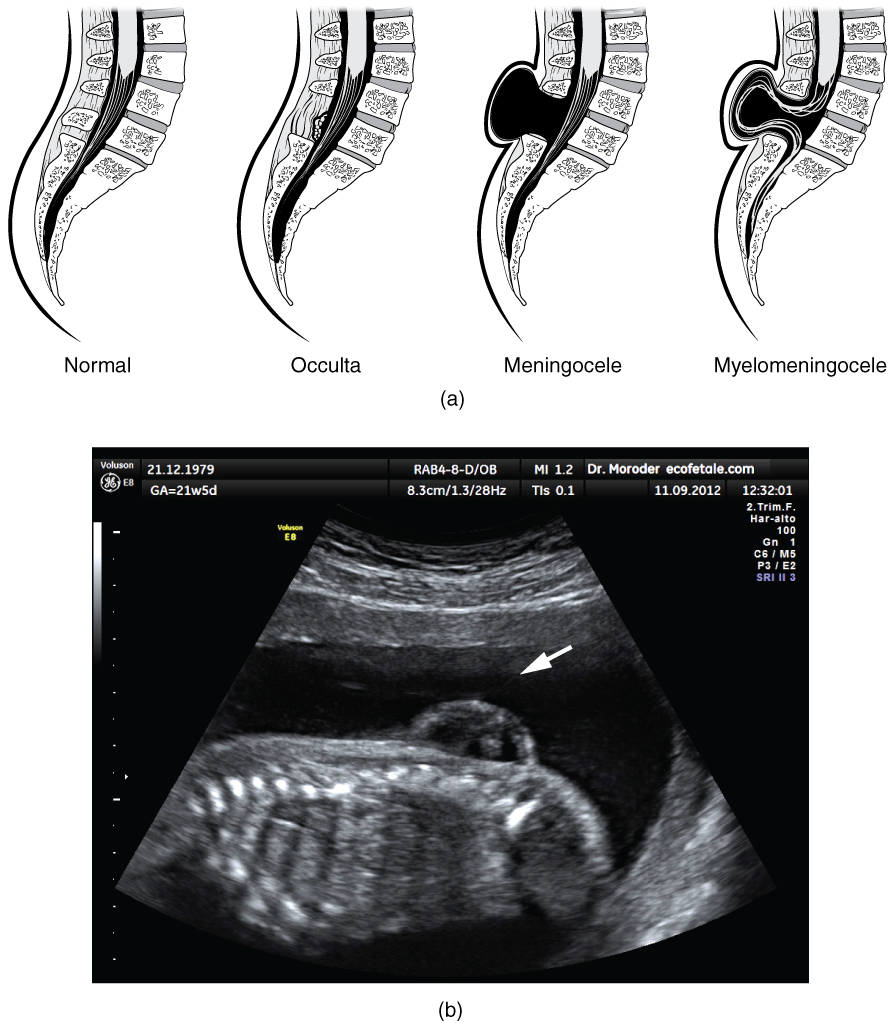

Early formation of the nervous system depends on the formation of the neural tube. A groove forms along the dorsal surface of the embryo, which becomes deeper until its edges meet and close off to form the tube. If this fails to happen, especially in the posterior region where the spinal cord forms, a developmental defect called spina bifida occurs. The closing of the neural tube is important for more than just the proper formation of the nervous system. The surrounding tissues are dependent on the correct development of the tube. The connective tissues surrounding the CNS can be involved as well.

There are three classes of this disorder: occulta, meningocele, and myelomeningocele (Figure 14.1.4). The first type, spina bifida occulta, is the mildest because the vertebral bones do not fully surround the spinal cord, but the spinal cord itself is not affected. No functional differences may be noticed, which is what the word occulta means; it is hidden spina bifida. The other two types both involve the formation of a cyst—a fluid-filled sac of the connective tissues that cover the spinal cord called the meninges. “Meningocele” means that the meninges protrude through the spinal column but nerves may not be involved and few symptoms are present, though complications may arise later in life. “Myelomeningocele” means that the meninges protrude and spinal nerves are involved, and therefore severe neurological symptoms can be present.

Often surgery to close the opening or to remove the cyst is necessary. The earlier that surgery can be performed, the better the chances of controlling or limiting further damage or infection at the opening. For many children with meningocele, surgery will alleviate the pain, although they may experience some functional loss. Because the myelomeningocele form of spina bifida involves more extensive damage to the nervous tissue, neurological damage may persist, but symptoms can often be handled. Complications of the spinal cord may present later in life, but overall life expectancy is not reduced.